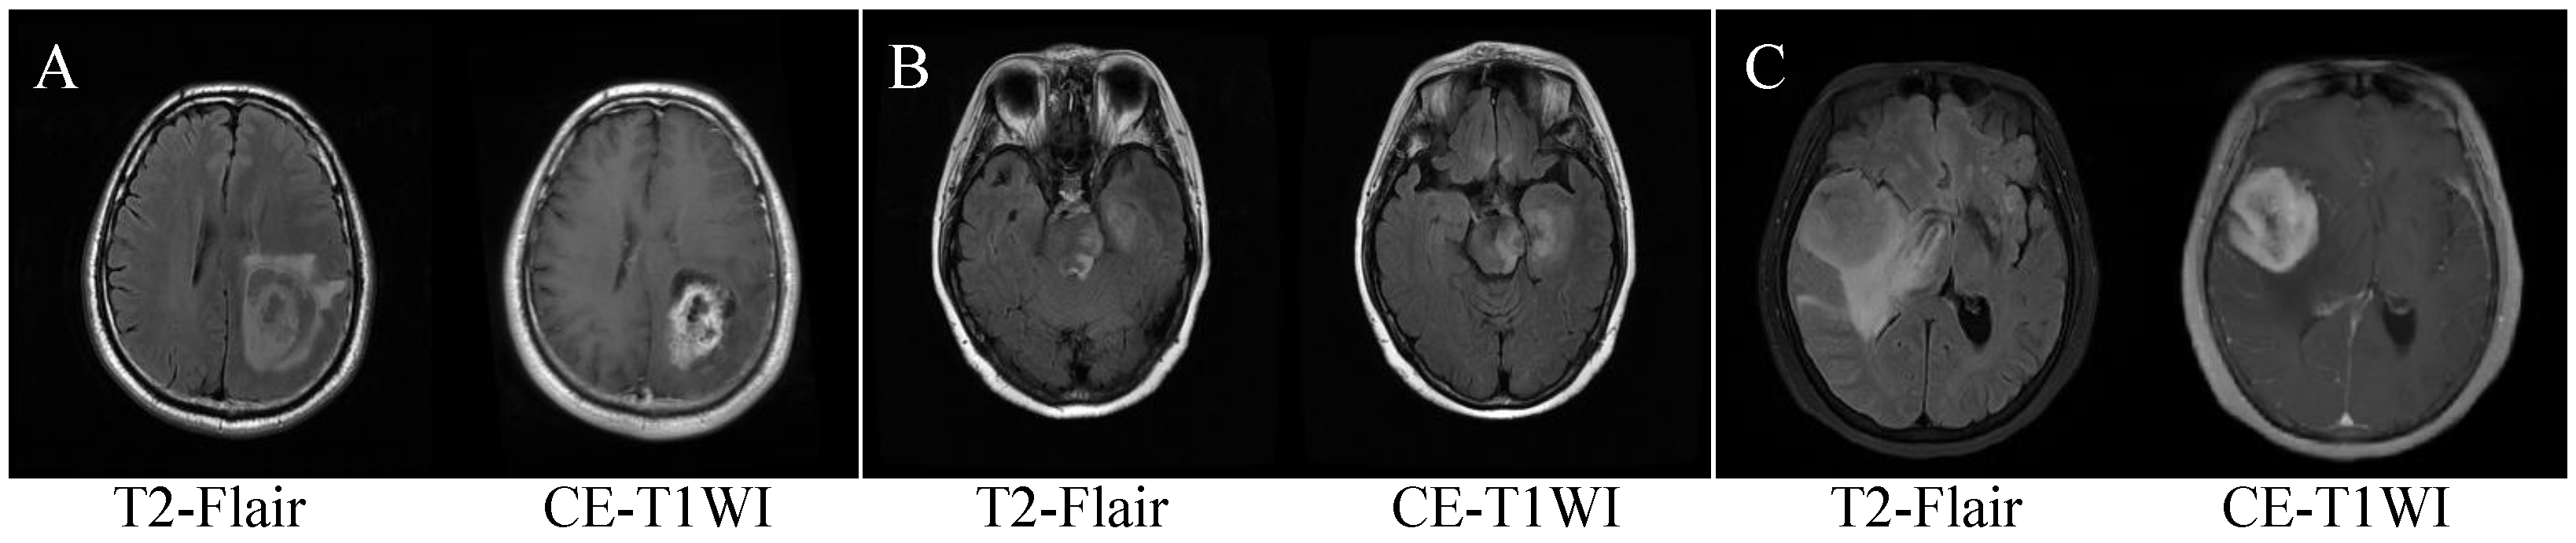

Appendix B. Figures